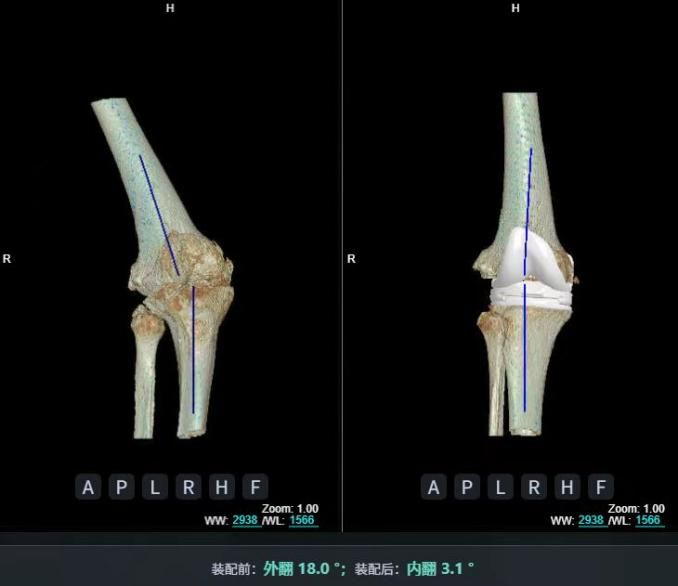

4.2 APTT-HTO脛骨高位截骨術(shù)

2025年7月,貴州醫科大學(xué)附屬醫院骨科團隊原創(chuàng )研發(fā)的腘肌前結節中脛骨高位截骨保膝術(shù)(Anterior Popliteus Transtibial Tuberosity-High Tibial Osteotomy, APTT-HTO)及其提出的脛骨結節分區與腘肌保護理論,登上了國際頂尖學(xué)術(shù)舞臺。該成果在全球最具影響力的專(zhuān)業(yè)會(huì )議之一——日本骨科協(xié)會(huì )第98屆年會(huì )上進(jìn)行了兩次學(xué)術(shù)發(fā)言。[8]

該手術(shù)具有經(jīng)皮微創(chuàng )、保留原生膝關(guān)節結構、符合階梯治療原則等優(yōu)勢,通過(guò)調整下肢力線(xiàn)可促進(jìn)部分軟骨再生,術(shù)后關(guān)節功能接近正常(如下蹲、爬山),患者還能從事中重體力勞動(dòng)。相比其他術(shù)式,其有效規避了髕骨低位、血管損傷、合頁(yè)骨折等潛在并發(fā)癥。

目前,APTT-HTO技術(shù)已成功應用于千余名患者,幫助保留自身膝關(guān)節。此類(lèi)保膝手術(shù)適用于單間室膝關(guān)節炎患者(如 “羅圈腿”),核心是通過(guò)調整力線(xiàn)糾正畸形,減輕磨損間室壓力、發(fā)揮健康間室作用,延長(cháng)膝關(guān)節壽命。若出現膝關(guān)節疼痛、保守治療無(wú)效且X線(xiàn)顯示關(guān)節間隙部分狹窄,建議及時(shí)就醫評估是否適合手術(shù)。